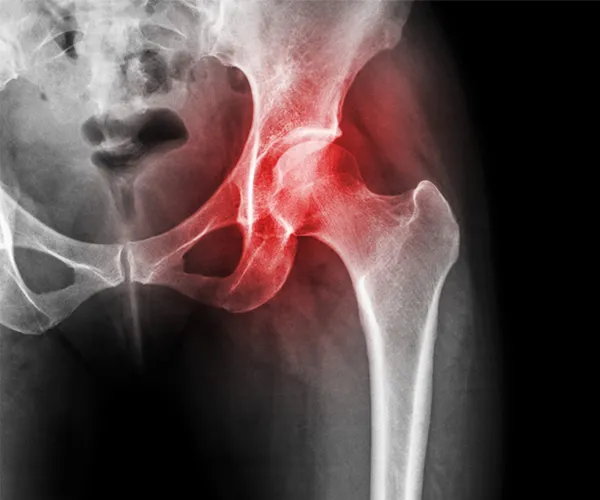

Avascular Necrosis Treatment in Jammu and Kashmir

Experience world-class orthopedic care at Impact Ortho Centre in Hyderabad. We serve patients from Jammu and Kashmir with advanced avascular necrosis treatment solutions, expert surgeons, and comprehensive rehabilitation programs for optimal recovery.